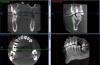

Slavik111 Опубликовано 5 июля, 2010 Автор Поделиться Опубликовано 5 июля, 2010 (изменено) Спасибо за ответ.Вот панорама.Вывод о том, что после удаления 16 и 17 образуется соустье, хирург сделал после просмотра 3Д снимка - это большая программа, ее сюда не закачать. Изменено 5 июля, 2010 пользователем Slavik111 Ссылка на комментарий

Slavik111 Опубликовано 5 июля, 2010 Автор Поделиться Опубликовано 5 июля, 2010 (изменено) Мне к сожалению снимки оттуда не выдернуть - это программа на диске которая сама демонстрирует свои снимки. Кажется формат DICOM. Но я попробую выдернуть (через копию экрана) пару продольных снимков этих зубов.Мне хирург сказал, что есть соустье или нет выяснится непосредственно после удаления. То естькак повезет. И если не повезет\, надо будет вскрывать пазуху и чистить гной перед ушиванием.Отличается ли эта операция по чистке от ЛОР операции на пазухе? (менее травмотична?)Можно ли при наличии какого-то минимального кол-ва гноя вообще не чистить пазуху у стоматолога, а просто - удалить, если соустья - зашить и пойти к ЛОРу промывать пункцией? Изменено 5 июля, 2010 пользователем Slavik111 Ссылка на комментарий

Slavik111 Опубликовано 5 июля, 2010 Автор Поделиться Опубликовано 5 июля, 2010 (изменено) Названия файлов - номера зубов. Еще 17-й зубhttp://saveimg.ru/show-image.php?id=b293d8...a9dc1c7d74bba31http://saveimg.ru/show-image.php?id=8c6420...92ba92c9a149318http://saveimg.ru/show-image.php?id=0660de...848084cfe5e2b22 Изменено 5 июля, 2010 пользователем Slavik111 Ссылка на комментарий

Slavik111 Опубликовано 6 июля, 2010 Автор Поделиться Опубликовано 6 июля, 2010 Согласен. + Все может оказаться еще проще, удалят, сообщения не будет, гайморит пройдет быстро. Насчет сообщения - я специально 4 снимка 17-го зуба приложил - там с моей точки зрения корни прямо в пазуху торчат (если это однородное пространство над корнем - пазуха).Или я не прав и это не пазуха? Большое спасибо за советы! Только что был на приеме у ЛОРа. 9-я пункция - вытянула немного (может 5 мл) шприцом желтого полупрозрачного секрета - сказала что киста. Затем промывала долго - 2 банки вылила - гной только вначале, примерно 1 чайная ложка (может меньше). По сравнению с позапрошлым разом - гораздо меньше.Извините, уважаемые, но несмотря на Ваши советы подписал отказ от госпитализации.След. пункция в четверг. ЛОР сердилась за мой отказ,сказала что меньше гноя уже не будет, но затем смягчилась (потому что ничего больше у меня не болит и насморка нет) и сказала что решим по результатам пункции в четверг.На самом деле я буду думать - я понимаю что в стационаре лучше, но раз все-таки меня соблазнили "более легким" путем - если без гноя то амбулаторно - то получается есть из чего выбирать. В черьверг, чувствую, уже не будет из чего выбирать Ссылка на комментарий